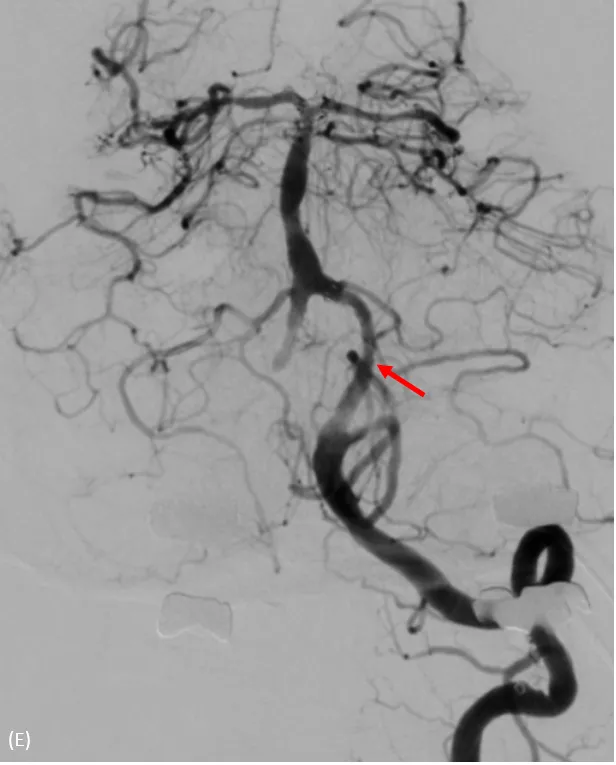

支架置放於左側椎動脈後,血流改善許多。大里仁愛醫院提供